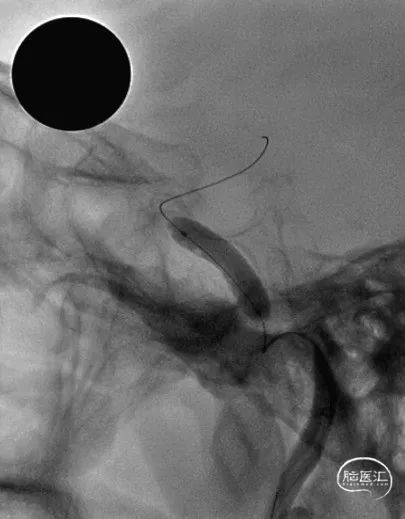

TRUST技术,6F 105cm Tethys®中间导引导管+5F 125cm Simmons 2+260cm软泥鳅导丝建立通路。

Tethys®中间导引导管内衬5F 125cm Simmons 2+260cm软泥鳅导丝,利用Tethys头端柔软特点同轴沿桡动脉方向裸奔至锁骨下。

Simmons 2至降主动脉,回撤导丝,弓上成袢。

Simmons 2勾选目标动脉,跟进导管,建立通路。应用TRUST技术经桡建立通路,无需交换,简便快捷,导管到位后,弓部支撑稳定,未出现打折现象。

上connect V18 300cm导丝做内支撑,保证后续通路稳定性。

3.0*12mm SacSpeed®球囊 6atm预扩1次后,造影发现狭窄处距离脉络膜前动脉很近,担心“雪犁效应”。

双V18导丝支撑,器械输送,将支架输送到位,精准定位下,避开脉络膜前动脉。

支架后多角度造影确认脉络膜前动脉未闭塞。

术前与术后。